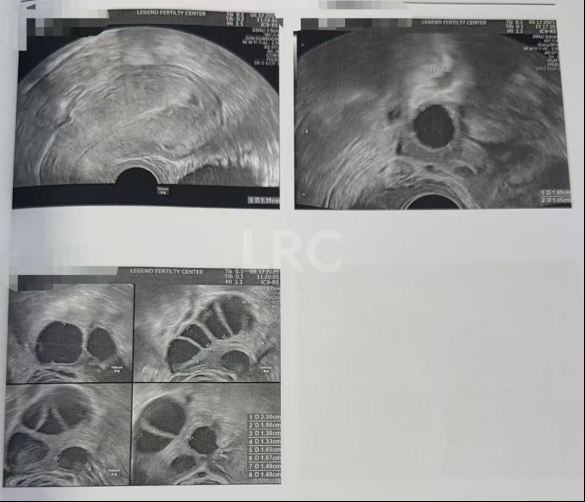

促排第七天

阴超检查:

- 右侧卵泡 9 颗可用 (20,17,16,16,15,15,13,13,12mm)

- 左侧卵泡 2 颗 (15,19mm)

子宫内膜厚度:10 mm

促排第八天

- 右侧卵泡 9 颗可用 (22,21,19,19,17,17,17,15,15mm)

- 左侧卵泡 1 颗 (19mm)

子宫内膜厚度:8.3 mm

第二轮促排结果

取卵及受精

取卵:7颗

成熟MII:6颗

ICSI受精成功:4颗

养囊成功:4颗